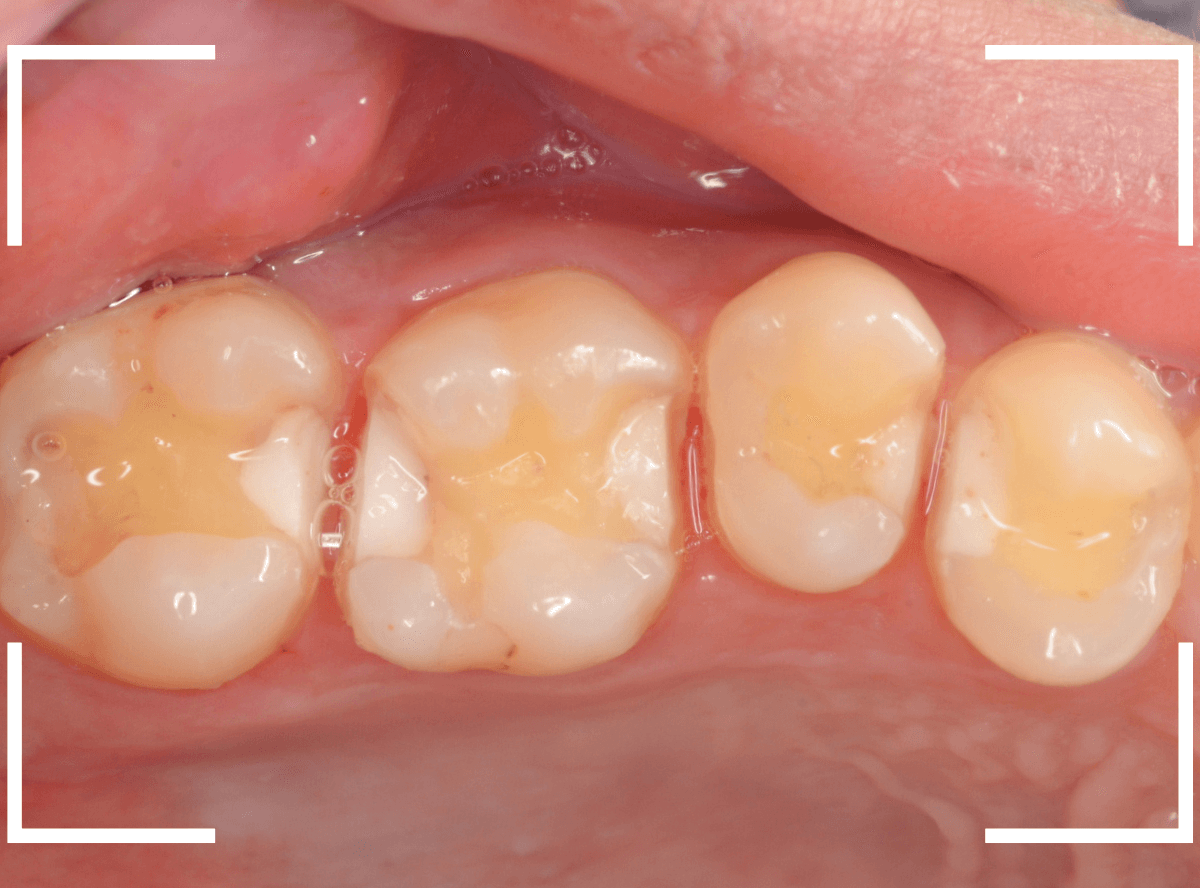

模型上で精密に製作します。

治療後の状態です。

自然な仕上がりで、患者さんにもご満足いただけました。